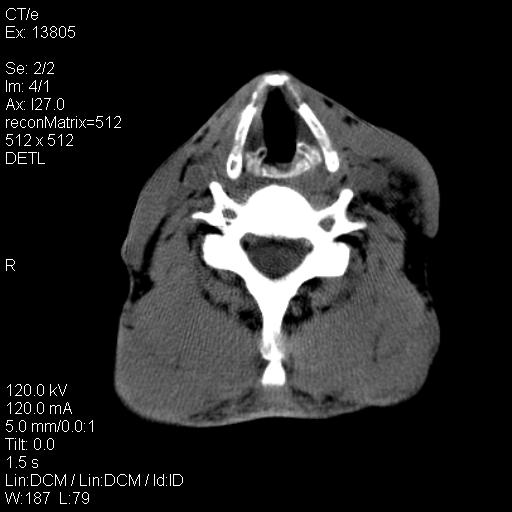

上腹部疼痛一月,呕吐10天,发现左侧颈部包快10天 胸部cr片未见明显异常。

左侧胸锁乳突肌下方、颈血管旁低密度肿块影,肿块密度尚均匀,边缘大部分清楚,邻近组织稍受压移位。考虑颈部神经鞘瘤可能性大。